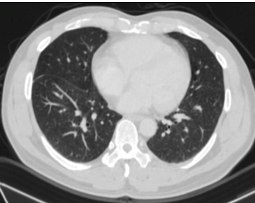

Chụp cắt lớp vi tính lồng ngực: Hình ảnh các nốt kính mờ rãnh liên thùy và màng phổi phải. Đám dải xẹp phổi thùy giữa phổi phải

Hình 7: Hình ảnh chụp cắt lớp vi tính lồng ngực sau điều trị, tổn thương u giảm kích thước sau 6 tháng điều trị (mũi tên vàng)